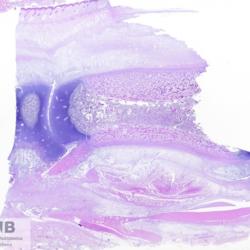

Lung

Pneumonia

Pneumonia - Embolic